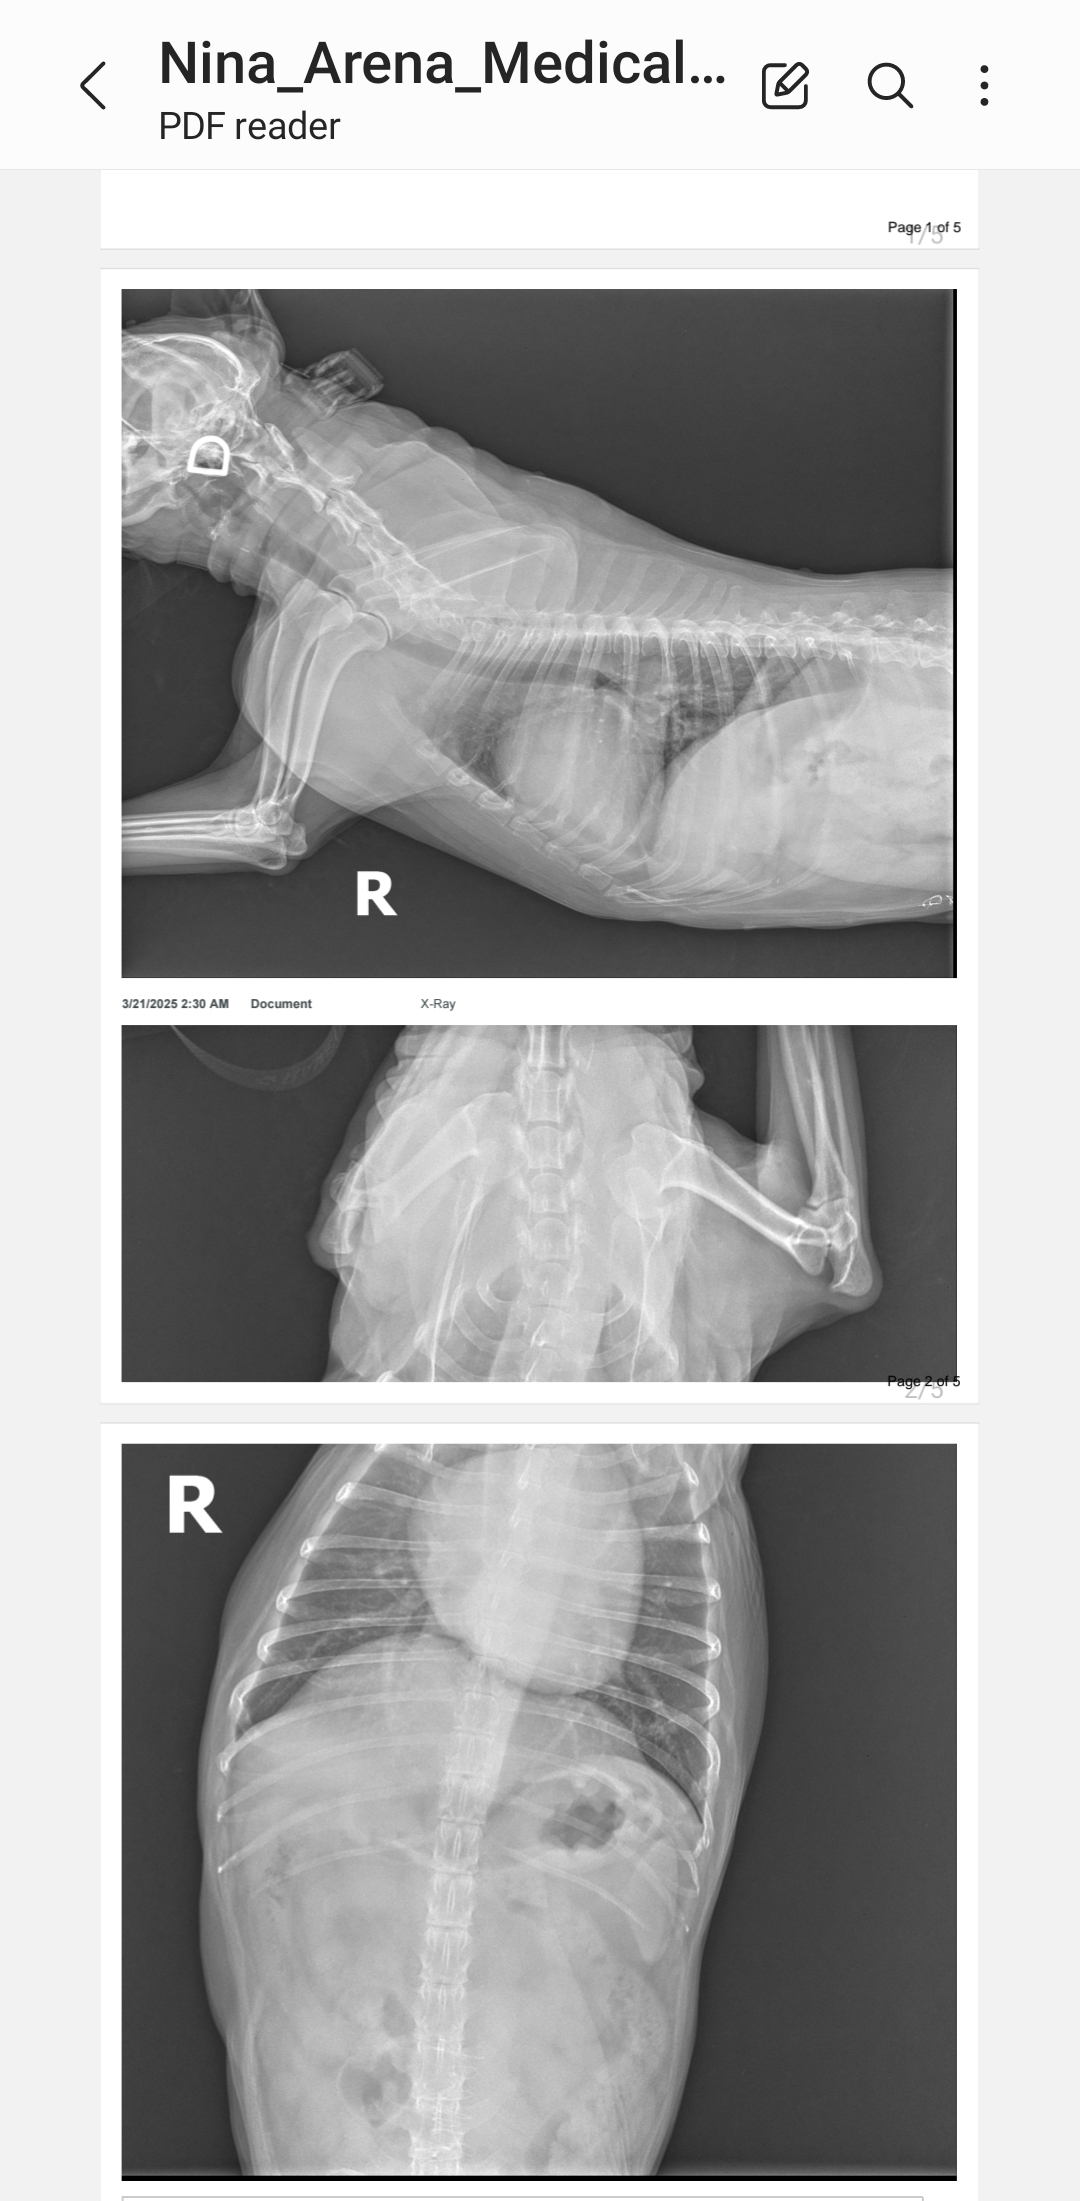

Hola me llamo Wilma Spreng y quiero solicitar ayuda para mi perrita que tiene una condición de corazón y neurológica. Ella tiene 14 años y ahora fue que salió con estas condiciones.

La llevé al veterinario para sus chequeos y hacerle los análisis y el tratamiento es muy costoso. Su condición de salud la está deteriorando rápidamente los gastos de los pasados tres meses han sido exorbitantes para mí presupuesto. Nina Arrena Spreng es mi vida y mi única compañía. Deseo darle una mejor calidad de vida y recurro a su buen corazón ❤️ . Cualquier ayuda es grande. Eternamente agradecida.